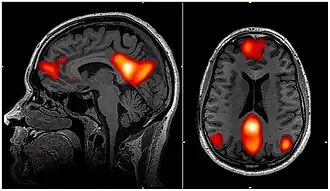

Default Mode Network

Als Default Mode Network (englisch DMN ‚Standard- oder Voreinstellungsmodusnetzwerk‘ bzw. sinngemäß ‚Ruhezustandsnetzwerk‘) bezeichnet man eine Gruppe von Gehirnregionen, die beim Nichtstun aktiv werden und beim Lösen von Aufgaben deaktiviert werden. Die Ruheaktivität dieser Hirnregionen lässt sich mit fMRT (v. a. Resting state fMRI), PET, EEG und MEG nachweisen.

Die Aktivität dieser Hirnregionen ist korreliert. Deshalb wird diese Gruppe von synchron aktiven Hirnregionen als Netzwerk aufgefasst. Das Netzwerk kann mit dem mathematischen Werkzeug Graphentheorie beschrieben werden. Zu den beteiligten Hirnregionen gehören z. B. der mediale präfrontale Cortex, Precuneus, Teile des Gyrus cinguli sowie – schwächer angebunden – der Lobulus parietalis superior des Scheitellappens und der Hippocampus. Die einzelnen Hirnstrukturen sind durch Weißesubstanzbahnen synaptisch miteinander verbunden.

Gezeigt werden konnte, dass die anatomische und funktionelle Konnektivität des Gehirns im Bereich des Default Mode Networks am stärksten überlappt. Dies wurde so interpretiert, dass der anatomische Aufbau des Gehirns eine Aktivierung des Netzwerks in Zuständen begünstigt, in welchen keine aufgabenspezifische Anforderung besteht (in Ruhezuständen).[12]